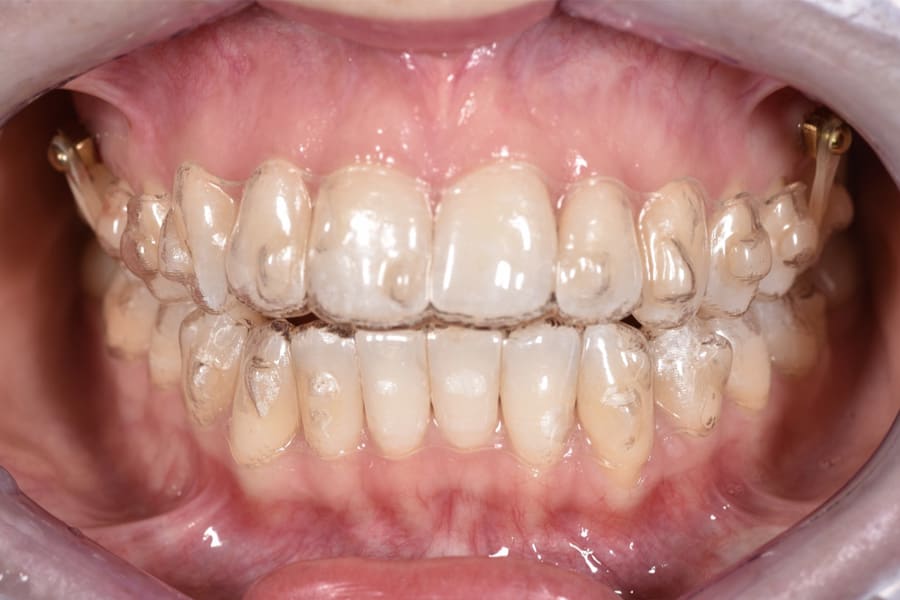

The orthodontic biomechanics are as follows: Skeletally anchored buccal and palatal TADs are positioned between the second premolar and first molar to provide vertical anchorage. Clear aligners are used for dental and dentoalveolar movement and remodeling to deliver controlled derotation, torque, curve-of-Spee adjustment, and anchorage-friendly staging. Elastics or chains to TADs add cranially directed force vectors for intrusion. Anterior vertical position is maintained to protect smile esthetics.3,7,17-21

A 31-year-old female patient presented with the following intraoral conditions: an anterior open bite, bimaxillary crowding, negative crown torque, early “black triangles,” and a thin phenotype/biotype with early recessions. Her extraoral situation included a gummy smile with high-lip mobility, asymmetric arch forms and posterior corridors, and incompetent lip closure (Figure 2 through Figure 4). Collectively, these factors increase esthetic and periodontal risk and favor posterior intrusion over anterior intrusion.4-8,12-16